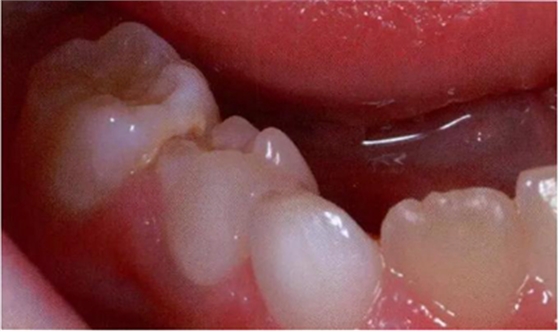

圖2:中度下沉的臨床像